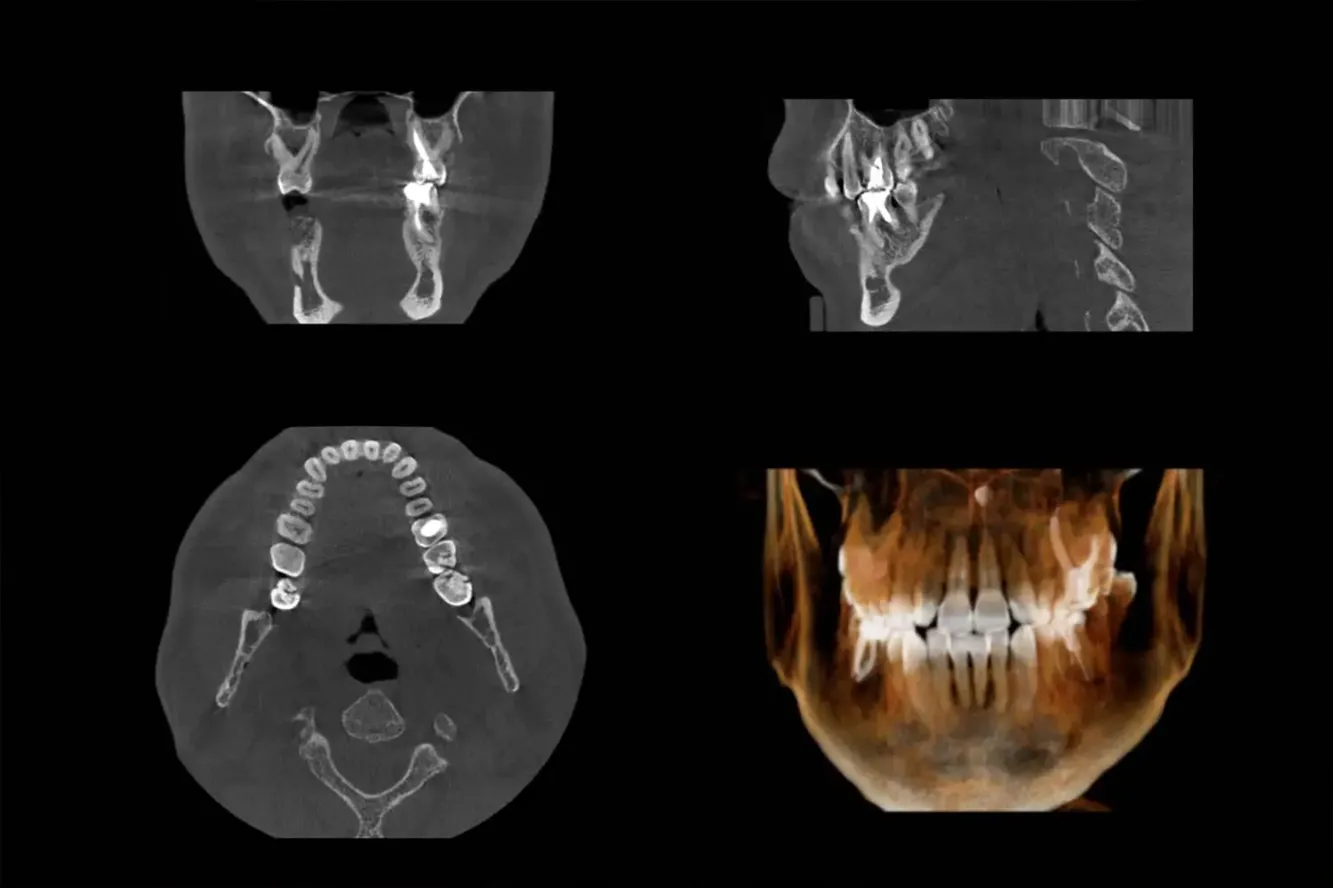

Tandheelkundige CT-scan

Wij hebben nu de beschikking over een tandheelkundige CT scanner (Cone Beam CT) in de praktijk. Hierdoor wordt het onderzoeken van complexe problematiek en Guided Implantology (implantaten) ook bij ons mogelijk.